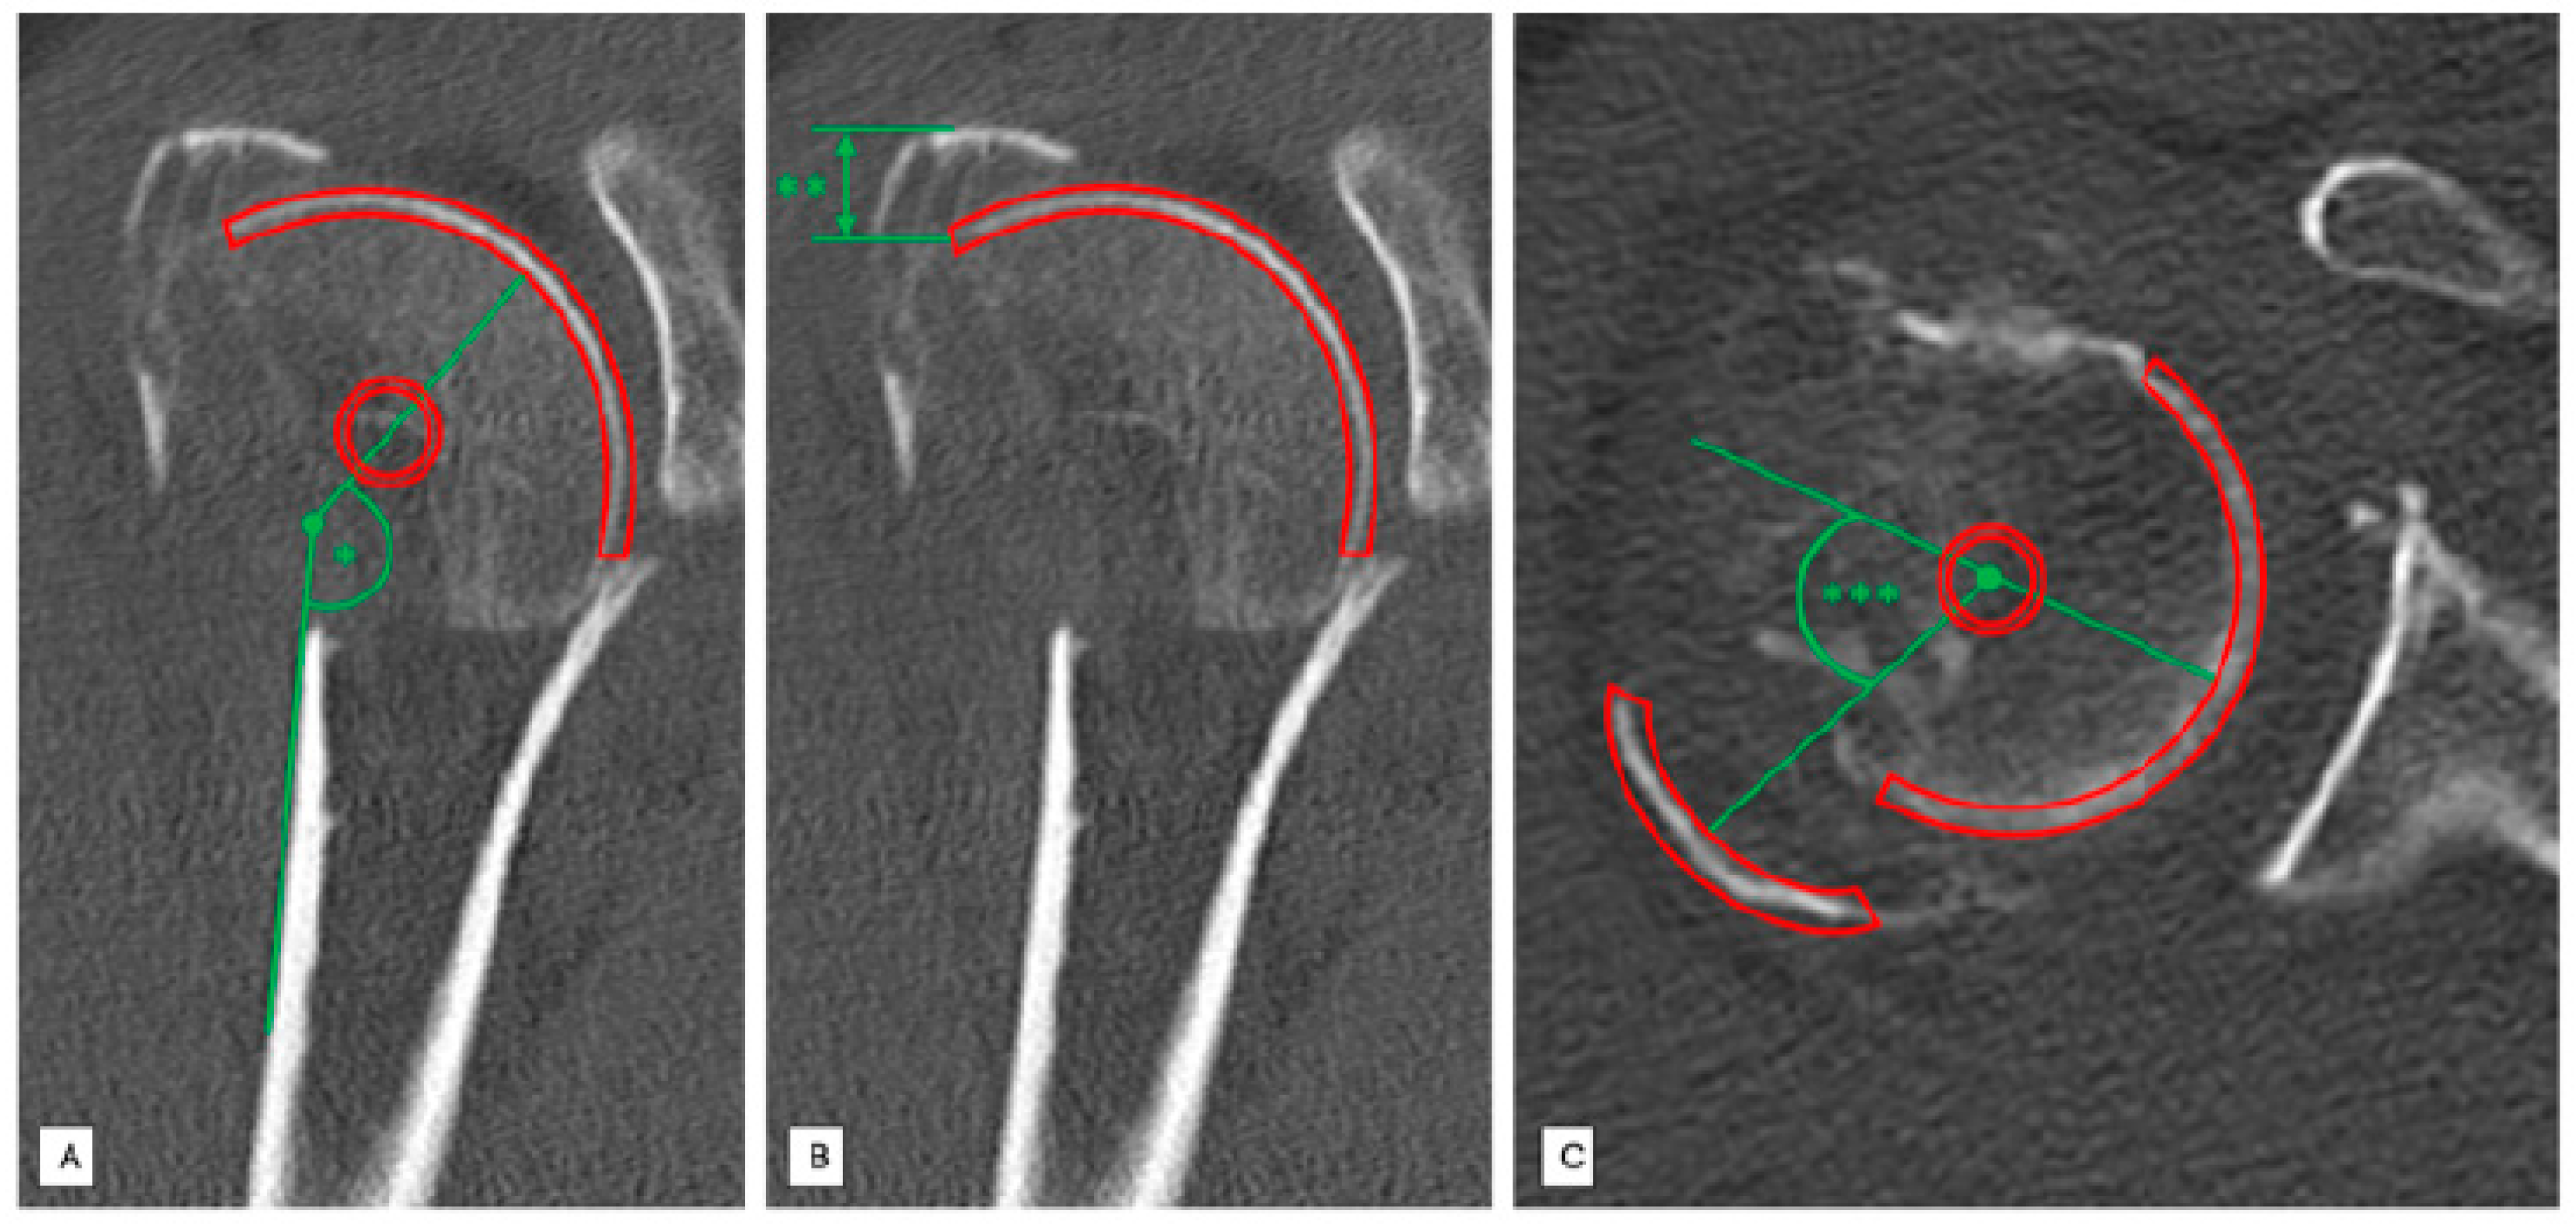

Figure 2.

Standardized radiological measurements in a patient with a Neer type 4 fracture injury of the right proximal humerus. (A) Standardized radiological measurement (*) of the head-shaft angle [°] in coronal slices. (B) Standardized radiological measurement (**) of the greater tuberosity displacement [mm] in vertical plane in coronal slices. (C) Standardized radiological measurement (***) of dorsal displacement [°] angle of the greater tuberosity in axial slices.

2.2. Head-Shaft Angle (HSA)

The head–shaft angle is created by a line parallel to the axis of the humeral shaft and perpendicular to the anatomical neck plane. We measured every head–shaft angle of the 121 included patients in the coronal plane to distinguish between varus (HSA < 125°) and non-varus fractures (HSA > 125°) (Figure 2A).

2.3. Position Determination of the Greater Tuberosity in the Vertical Plane (Cranial Displacement)

The displacement of the greater tuberosity in the vertical plane was measured using coronary reconstructions. Firstly, the most distant part of the fragment and the initial attachment of this fragment were identified and the distance between these two was quantified [mm] (Figure 2B).

2.4. Position Determination of the Greater Tuberosity in the Horizontal Plane (Dorsal Displacement)

The position of the greater tuberosity in the horizontal plane was evaluated by analyzing axial CT slices. Therefore, determination of dorsal displacement of the greater tuberosity was measured using an angle [°] formed by a line that passes the original insertion of the greater tuberosity and a line through the center of the greater tuberosity fragment (Figure 2C).